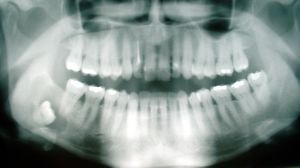

ضرس العقل، أو الضرس الثالث، هو ضرس يقع في أخر الفك، وهو آخر ما ينشأ من الأسنان في الإنسان. ويوجد ضرس عقل واحد في كل ركن من أركان الفم. ويبدأ في الظهور ما بين سن 17 و25.[1] Most adults have four wisdom teeth, but it is possible to have more—in which case they are called supernumerary teeth—or fewer—a condition called hypodontia. ويؤثر نمو ضرس العقل على باقي الأسنان، أو قد يسبب "إعوجاجهم".[2] وعادة ما يتم خلع ضرس العقل عندما يعاني المريض من بعض المشكلات.